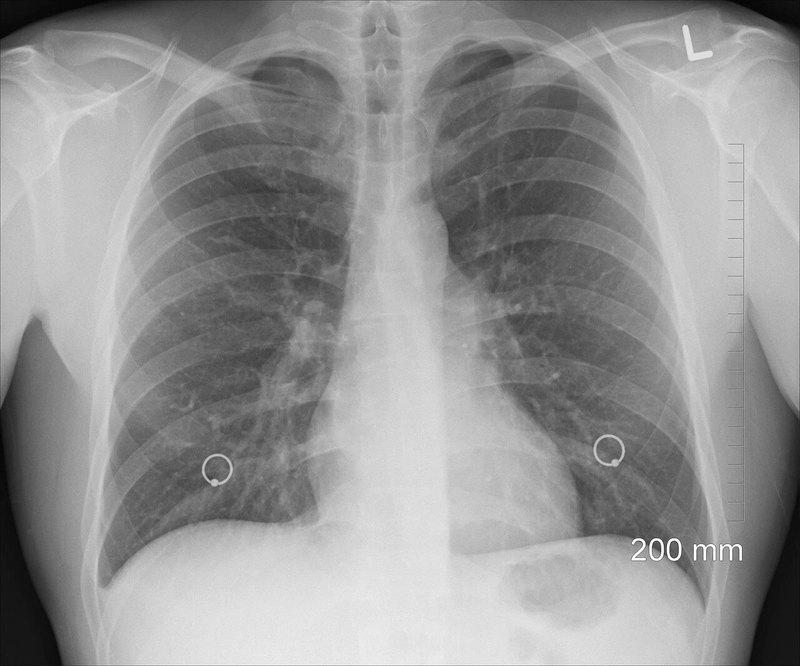

恶性胸腔积液是晚期癌症的常见并发症,严重影响患者生活质量(呼吸困难、咳嗽、胸痛)。其管理目标是缓解症状、改善生活质量、减少积液复发,并尽可能简化治疗流程。管理策略需个体化,需考虑患者的症状、体力状态(PS)、预期寿命、原发肿瘤类型及对全身治疗的反应、肺复张的可能性以及患者意愿。以下是恶性胸腔积液的主要管理方法:1.诊断性胸腔穿刺术: ·这是首要步骤,用于: ·确认诊断:通过胸水生化(蛋白、LDH、葡萄糖、pH)、细胞学检查或胸膜活检(如有必要)明确积液为恶性。 ·缓解症状:初次大量积液导致严重呼吸困难时,引流积液可迅速缓解症状。 ·注意:单次穿刺引流后积液通常会快速复发(平均4.7天)。2.治疗性胸腔穿刺术(反复穿刺): ·适用情况:预期寿命很短(数周)、体力状态极差(PS很差)、积液生长缓慢、患者拒绝其他有创操作、肺无法复张(无法进行胸膜固定)。 ·优点:操作相对简单、创伤小。 ·缺点:积液复发快,需反复穿刺,增加痛苦、感染和出血风险;反复丢失蛋白;可能导致包裹性积液。3.胸腔置管引流: ·放置小口径(如10-14Fr)引流管进入胸膜腔,连接引流袋或负压吸引瓶。 ·目的: ·充分引流:为后续胸膜固定术做准备,需尽可能排空积液使肺复张。 ·控制症状:对不适合胸膜固定术的患者,可长期留置引流管(见下)。 ·管理:需监测引流量和性状,通常在引流量<150ml/天且胸片证实肺已复张时,可考虑行胸膜固定术或拔管(若仅用于引流)。4.胸膜固定术: ·目标:通过药物(硬化剂)刺激胸膜产生炎症和粘连,使脏层和壁层胸膜融合,消灭胸膜腔空间,阻止积液再积聚。 ·关键前提:肺必须能够完全复张(脏层胸膜无增厚包裹肺组织)。 ·方法: ·胸腔镜下(VATS):首选方法。可在直视下充分引流积液、松解粘连、喷洒硬化剂(常用滑石粉粉剂喷洒)。成功率高(>90%),可同时进行胸膜活检,住院时间短。但需全麻,对体力状态要求稍高。 ·经胸管注入生物反应调节剂:经充分引流确认肺复张后,经胸管注入硬化剂白介素-2、榄香烯乳注射液等夹管1-2小时后开放引流或负压吸引。成功率较VATS低(约70-80%)。 ·常用硬化剂: ·无菌滑石粉:最有效,成功率最高(粉剂喷洒优于混悬液)。需警惕罕见但严重的并发症(急性呼吸窘迫综合征、低氧血症,多见于大剂量使用)。 ·副作用:胸痛、发热、恶心等。5.长期/间歇性留置胸腔引流管: ·放置带皮下隧道的专用引流管(如PleurX/PleuralCath)。 ·适用情况: ·肺无法复张(无法行胸膜固定术)。 ·预期寿命中等(数月)。 ·患者希望居家管理积液。 ·方法:门诊置管,患者或家属可在家定期(通常隔日或根据症状)连接真空瓶引流积液(每次引流量常限制在1000-1500ml以内)。 ·优点: ·有效控制症状,避免反复住院穿刺。 ·部分患者(约40-50%)在长期引流后可能自发形成胸膜固定。 ·提高生活质量,方便居家护理。 ·缺点:有导管相关并发症风险(感染、堵塞、局部疼痛、肿瘤种植);需要患者/家属配合护理。6.全身治疗: ·如果恶性胸腔积液是由对化疗、靶向治疗或免疫治疗高度敏感的肿瘤(如小细胞肺癌、淋巴瘤、乳腺癌、某些基因突变的非小细胞肺癌)引起,且患者体力状态允许,有效的全身治疗是控制MPE的基础和首选。 ·全身治疗起效后,积液可能明显减少甚至消失,无需立即进行局部干预或可简化局部治疗。7.支持治疗: ·氧疗:改善低氧血症。 ·镇痛:控制胸痛。 ·营养支持:改善一般状况。 ·姑息治疗:对于终末期患者,重点在于最大程度缓解呼吸困难、疼痛和焦虑。管理流程概要(需个体化):1.诊断:胸腔穿刺确诊MPE并缓解急性症状。2.评估: ·患者体力状态(PS)、合并症、预期寿命。 ·原发肿瘤类型、分期、对全身治疗的反应性(是否敏感且未耐药)。 ·胸水生长速度。 ·胸部影像学(CT最佳)评估肺是否可复张、有无包裹。 ·患者意愿及居家护理能力。3.决策: ·预期寿命极短/PS极差/积液生长极慢/拒绝有创操作:考虑观察或必要时反复胸腔穿刺。 ·肿瘤对全身治疗敏感且PS允许:优先开始或优化全身治疗。根据疗效决定是否需要局部干预。 ·肺可复张: ·首选:胸腔镜下(VATS)滑石粉喷洒胸膜固定术(尤其预期寿命>3-6月,PS较好)。 ·次选:经胸管注入硬化剂(如滑石粉混悬液、博来霉素等)。 ·肺无法复张: ·预期寿命中等(数月):留置隧道式胸腔引流管,居家间歇引流。 ·预期寿命短/PS差:考虑反复穿刺或短期留置普通胸管引流缓解症状。 ·治疗失败或复发:评估原因(肺是否复张?硬化剂是否有效?)。可尝试更换硬化剂、再次胸腔镜手术、或转为留置隧道式引流管。重要注意事项:·多学科协作:MPE管理需要呼吸科、肿瘤科、胸外科、放射科、姑息治疗团队的紧密合作。·个体化:没有绝对“最好”的方法,必须根据患者的具体情况权衡利弊。·沟通:充分与患者及家属沟通各种治疗方案的预期效果、风险、利弊、操作过程和后续护理要求,共同决策。·关注生活质量:治疗的核心目标是缓解症状,改善生活质量,而非追求影像学上的完全“治愈”。·并发症管理:注意预防和处理各种操作(穿刺、置管、固定术)的并发症,如气胸、出血、感染、疼痛、复张性肺水肿等。总之,恶性胸腔积液的管理是一个综合性的姑息治疗过程。胸腔镜下滑石粉喷洒胸膜固定术和留置隧道式胸腔引流管是当前最主流的两种有效方法,选择哪种取决于肺复张的可能性和患者的整体状况。全身治疗在敏感肿瘤中具有基石地位。希望这些信息能帮助您或您关心的患者更清晰地了解应对策略。面对晚期癌症带来的挑战,专业医疗团队的支持和个体化治疗规划至关重要,请务必与医生深入讨论最适合的具体方案。

恶性胸腔积液是肺癌晚期患者最常见的并发症之一,也就是大众常说的“胸水”。超过一半的肺癌患者可能出现不同程度的恶性胸腔积液,其中晚期肺癌患者出现恶性胸腔积液的比例超过60%,且症状大多较为严重。恶性胸腔积液是一种怎样的并发症呢?恶性胸腔积液是指肺癌患者的胸腔积累了大量的组织液和淋巴液,且无法正常吸收或排出。大量的积液会压迫人体的脏腑,尤其是对肺部造成很大压力,因此,恶性胸腔积液的患者一般都会出现胸闷、气短等症状,尤其当积液量较大时(超过1500ml),患者会出现严重的呼吸困难,如果不及时治疗,很可能危及到患者生命。 当出现恶性胸腔积液时应该怎么做呢?首先无论症状轻重,都要及时就医并遵医嘱治疗。临床中治疗肺癌合并恶性胸腔积液以缓解患者症状为主要治疗目的,胸腔穿刺引流是最常用的治疗方法,通过胸部插管引流,让胸腔中的积液顺着引流管排出体外,从而缓解患者的症状。对患者而言,在治疗的同时要尽量保持低盐饮食,并且多吃一些易消化、易吸收的高蛋白食物。